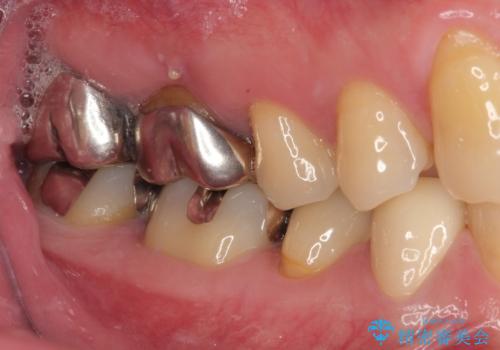

拡大鏡視野下で虫歯を除去しオールセラミッククラウンに適した形に整えました。

歯と歯茎の間に圧排糸と言われる糸を入れてシリコーン印象材にて型どりをしました。

審美面、機能面共に満足していただけました。

順次、後ろにある不適合のメタルインレーの部位をやり替えていく予定です。